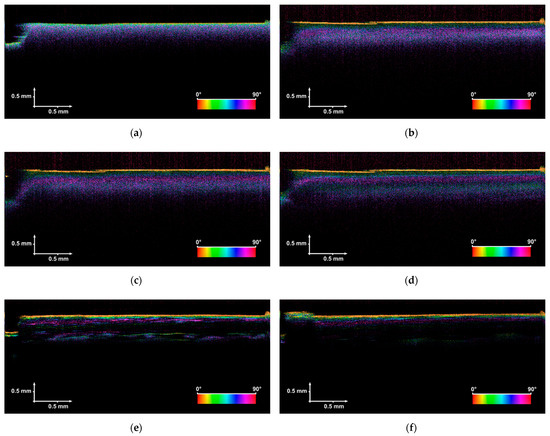

During the experiment, 23 PS-OCT images were collected and processed for further analysis: 8 for sample B24h_OCT (taken in the first 24 h) and 15 for sample B14D_OCT (taken in the first 14 days). A representative set of the measurement results, which express the observed trends and support the conclusions, is shown in Figure 4.

Figure 4.

PS-OCT images of the tested bones taken in the first 24 h (sample B24h_OCT, figures (a–d)) and 14 days (sample B14D_OCT, figures (e,f)); (a) the image taken at the beginning of the experiment (the bone has not been exposed to the acetic acid), (b) after 1 h; (c) after 3 h; (d) after 24 h, (e) after 7 days, (f) after 14 days.

The first attempt at the analysis was based on subjective evaluation of the PS-OCT cross-sectional images. Following, two main trends are observed. Firstly, exposure of the sample to acetic acid reduces the optical scattering and absorption effects inside the tested bone. This has been observed for both B24h_OCT and B14D_OCT samples as a decrease in the level of backscattered light from the bone’s inner structure in exposure time. To underline this conclusion, one should compare the images in Figure 4. The PS-OCT image, labeled as (a), was taken at the beginning of the experiment when the bone was not affected by the acid. Comparing this PS-OCT image with (b), (c), and (d), the lower intensity of backscattered light from the sample’s subsurface structure and higher penetration depth can be noticed. This phenomenon increases especially after a longer exposure time (longer than 1 or 2 days), which is confirmed by PS-OCT images (e) and (f) in Figure 4. Some valuable conclusions can be derived from the polarization-sensitive measurements. The first PS-OCT image in the series of B24h_OCT measurements expresses a random change in the retardation angle (the sample has not been influenced by acid yet), which suggests the light depolarizing nature of the evaluated structure. After 24 h of exposure of the bone to the acid, regular color stripes can be seen, which leads to the conclusion that the sample exhibited some birefringent effects. This and the scattering phenomena in the bones have been proceeded to quantitative analysis, described in the next session.